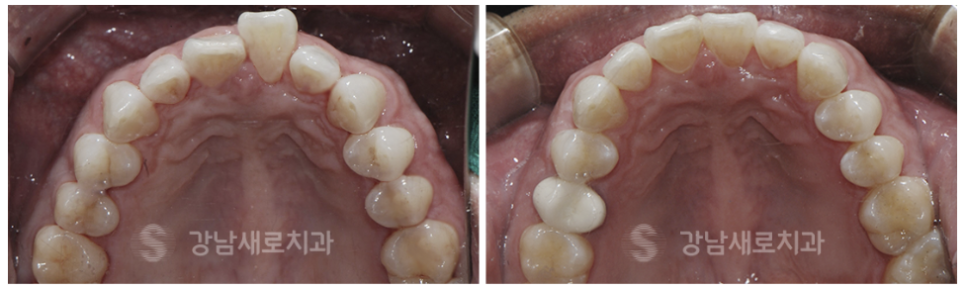

치열이 고르지 못하고 삐뚤빼뚤한

전치부와 송곳니까지

교정을 원하는 치아를 선택하여

치아 라인뿐 아니라 악궁 라인까지

빠르게 개선이 가능합니다.